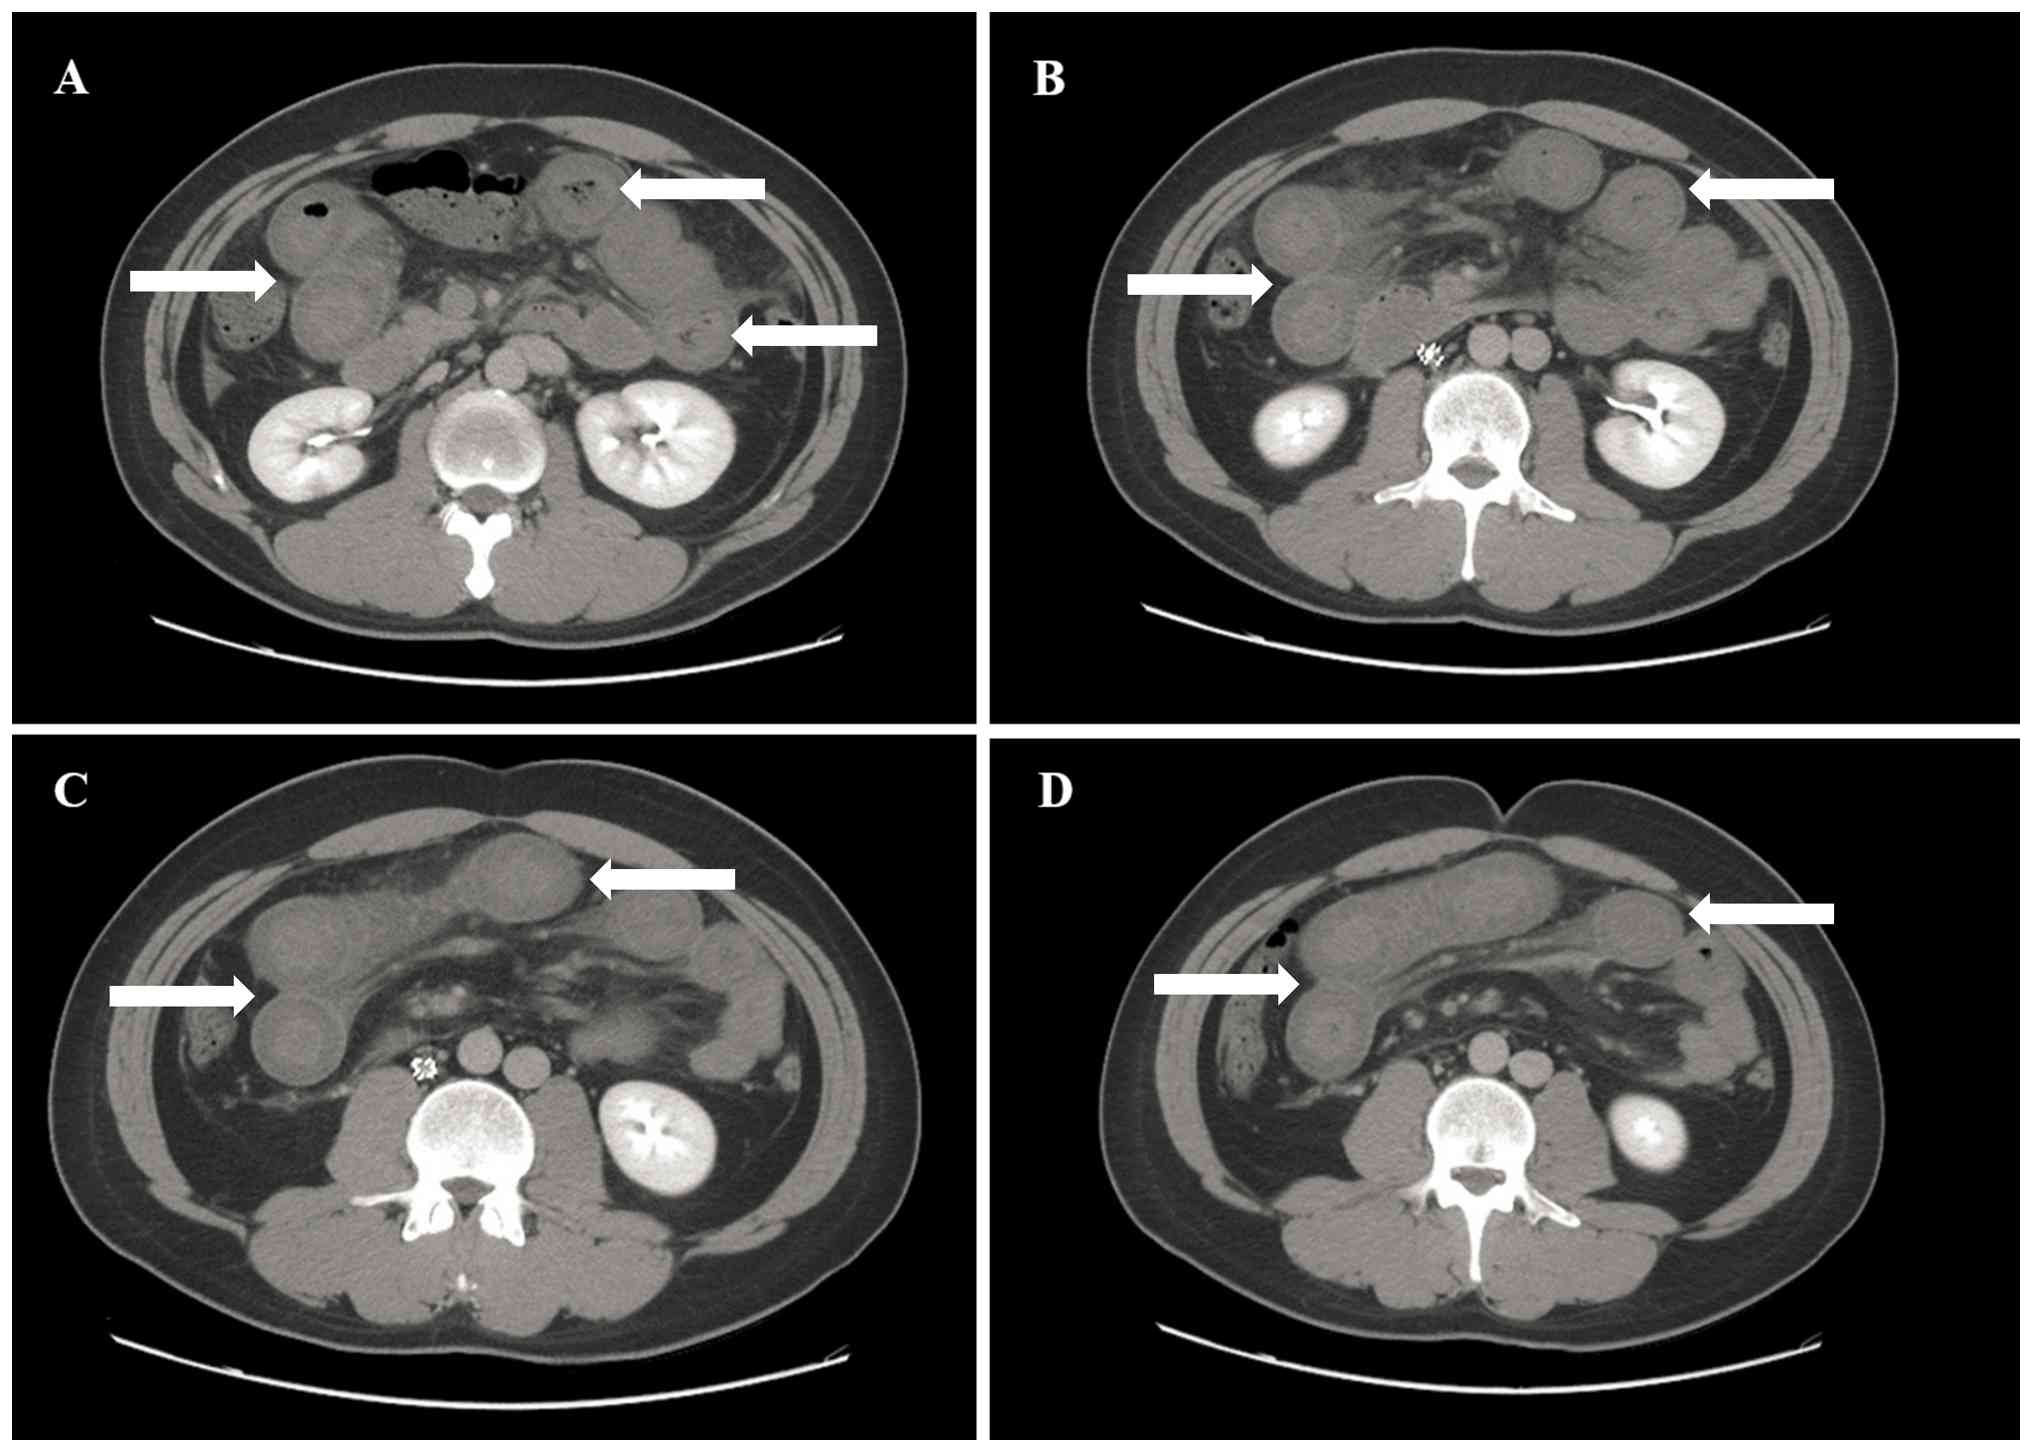

An emergency upper GI endoscopy was performed within 1 h of hematemesis, which revealed no source of bleeding in the esophagus, stomach or duodenum. Furthermore, an abdominal ultrasonography revealed moderate ascites, which was drained under ultrasound guidance, yielding ~500 ml of bloody fluid. An abdominal CT scan exhibited extensive dilation of the small intestine in the upper abdomen, with thickened intestinal walls also observed (maximum thickness, 0.9 cm; Fig. 1).

Consecutive axial contrast-enhanced

abdominal CT scans (A-D), showing extensive dilation of the small

intestine in the upper abdomen, with thickened intestinal walls

(arrows indicate dilated small intestinal loops with thickened

walls).

Figure 1

Consecutive axial contrast-enhanced abdominal CT scans (A-D), showing extensive dilation of the small intestine in the upper abdomen, with thickened intestinal walls (arrows indicate dilated small intestinal loops with thickened walls).